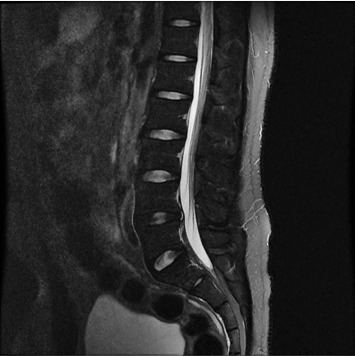

향상된 영상화질

향상된 대조도

노이즈 개선

모든 해부학적 부위 적용가능

standard

384 x 256 (4 NEX)

3:02 minIAI (Innovative AI)

384 x 256 (2 NEX)

1:30 minReduced Scan Time

IAI는 AI Deep learning을 통해 기존 장비의 촬영 프로토콜을 최적화합니다.

기존 프로토콜 대비 촬영 시간을 50% 단축시키며, 이미지 퀄리티는 증가합니다.